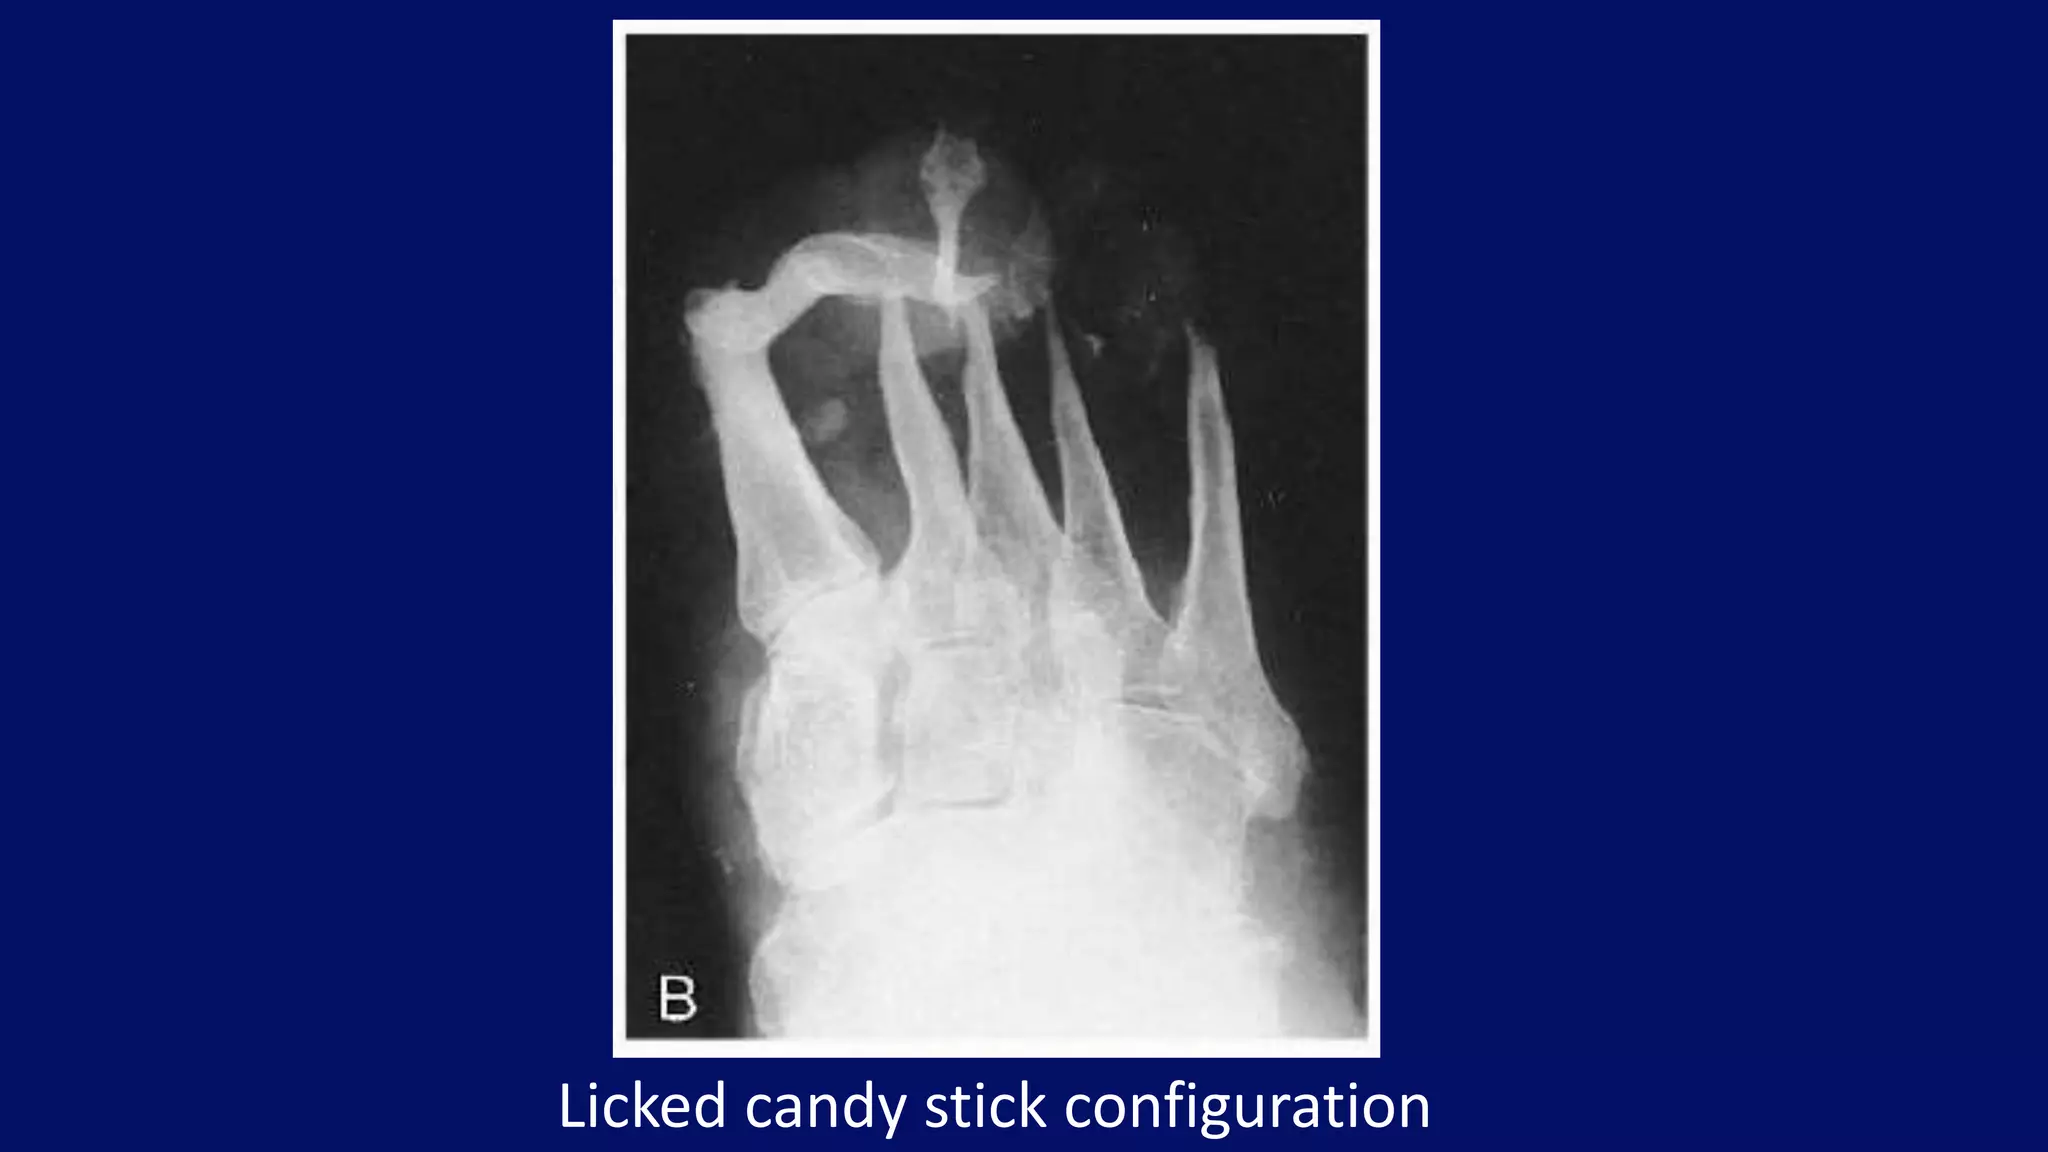

Licked candy stick configuration

• #52 Diabetes, Foot. Note that the distal metatarsals are tapered, producing a licked candy stick configuration.